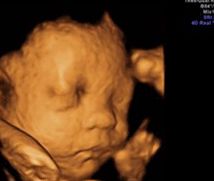

• -郑州万安妇产医院

相册

巴啦啦小魔仙 上传于 18-10-25 | 报错